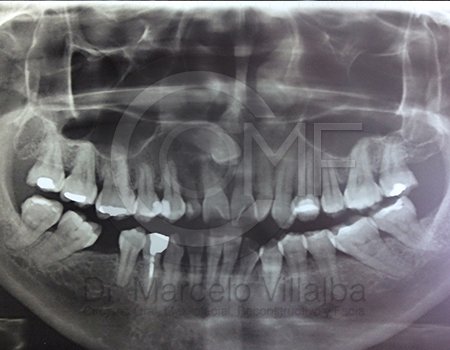

Generalmente en el momento de su erupción presentan procesos inflamatorios en la zona posterior de la cavidad oral, infección, dolor, movilidad de órganos dentarios, mal sabor en boca, mal olor en boca (halitosis), infección, incluso edema (aumento de volumen en tejido blando de la cara y/o boca) y complicaciones si no son atendidos. En el apoyo de diagnóstico se pueden requerir radiografías panorámicas y hasta tomografía en caso de ser necesarios.

Para el tratamiento de estas patologías se necesita en forma inicial estudios de laboratorio, radiografías o tomografías, estos estudios serán solicitados por el especialista a cada caso en particular, siendo su tratamiento quirúrgico bajo la modalidad de anestesia local o anestesia local más sedación consciente se puede realizar el procedimiento en corto tiempo y buen pronóstico.